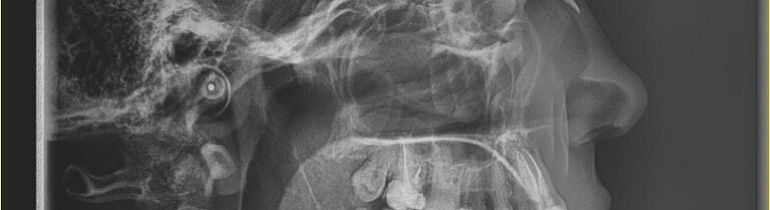

ТРГ Телерентгенография черепа в одной проекции

ЧТО АНАЛИЗИРУЕТСЯ НА ТРГ?

• Положение челюстей относительно друг друга

• Углы наклона зубов и их соотношение

• Профиль лица и эстетические параметры

• Дыхательные пути и их проходимость

• Ростовой потенциал у детей и подростков